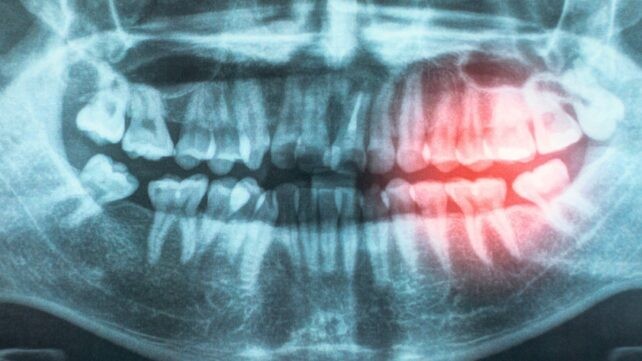

Une revue du comité de prévention des maladies cardiovasculaires de l’American Heart Association renforce l’idée que préserver la santé des gencives peut protéger contre les maladies cardiaques. S’appuyant sur une décennie de littérature qui comprend des investigations génétiques, des essais cliniques et des tests en laboratoire, leur rapport met à jour leur déclaration scientifique de 2012 et apporte des preuves encore plus solides qu’éviter l’ASCVD par une meilleure hygiène bucco-dentaire mérite d’être exploré. « Votre bouche et votre cœur sont connectés », déclare le cardiologue pédiatrique Andrew Tran. « La maladie des gencives et une mauvaise hygiène bucco-dentaire peuvent permettre aux bactéries d’entrer dans la circulation sanguine, provoquant une inflammation qui peut endommager les vaisseaux sanguins et augmenter le risque de maladie cardiaque. » L’ASCVD demeure la principale cause de mortalité mondiale, et si l’amélioration de l’hygiène bucco-dentaire pouvait potentiellement être une des façons d’empêcher que cela se produise, cela mérite d’être étudié.

Basée sur une décennie de littérature qui inclut des investigations génétiques, des essais cliniques et des tests en laboratoire, leur rapport actualise leur déclaration scientifique de 2012 et fournit des preuves encore plus solides que les problèmes cardiaques déclenchés par l’athérosclérose (ASCVD) sont étroitement associés à la maladie parodontale. Dans leur revue, les chercheurs ont exploré les causes possibles de l’association, notamment la probabilité que les bactéries entrent dans le corps par les gencives exposées et endommagées, contribuant à l’inflammation chronique. « Il existe de fortes preuves que le traitement de la maladie parodontale améliore des mesures intermédiaires, telles que la pression artérielle, le taux de cholestérol HDL et les marqueurs inflammatoires, » écrivent les chercheurs dans leur article publié. « Cette découverte est importante car ces mesures augmentent le risque cardiovasculaire futur et fournissent un lien possible entre la maladie parodontale et l’ASCVD. » Certaines des études analysées incluaient des détails sur des sujets remontant à l’enfance, montrant que prendre soin de ses dents dès le plus jeune âge pourrait réduire le risque de problèmes cardiaques plus tard. Le panel appelle à des études plus détaillées et à plus long terme pour approfondir les recherches existantes sur la santé cardiaque et la santé bucco-dentaire, y compris la question de savoir si des traitements pour une maladie parodontale établie réduisent la probabilité de l’ASCVD — une donnée utile pour évaluer la causalité.